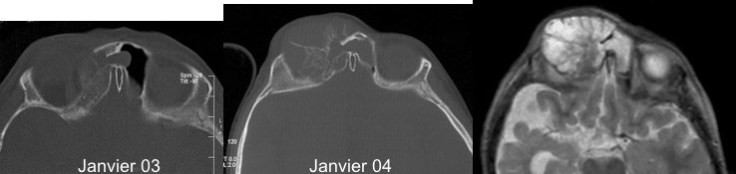

le syndrome de Solomon

il peut s’associer à des lésions de remaniement osseux ressemblant à un kyste anévrysmal comme ci-dessous.

ces lésions sont apparentées à celles du syndrome de Schimmelpenning